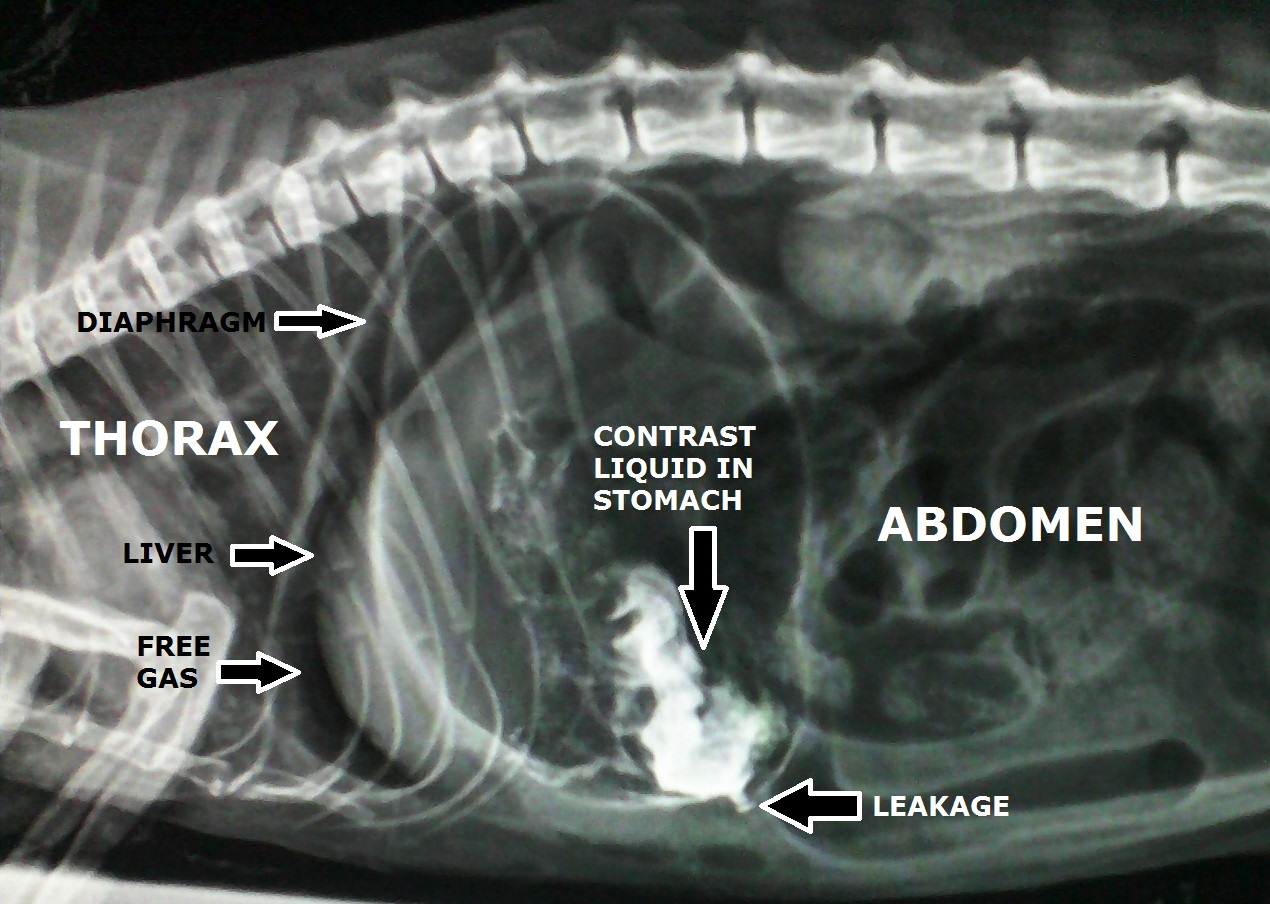

VeteriSilvia Peritonitis in a cat/peritonitis en un gato Cat Gi Infection Symptoms of gastroenteritis in cats. Cats may experience gastroenteritis if they eat things that upset their stomach, like grass. It can be caused by something as minor as a change in your cat’s diet to more. Here are some common gi problems in cats and what to do about them. Exposure to feces of infected. Cats with stomach ulceration may. Cat Gi Infection.

From veterisilvia.blogspot.com

VeteriSilvia Peritonitis in a cat/peritonitis en un gato Cat Gi Infection Gastrointestinal ulceration is often associated with tumors in cats, but the cause can also be unknown. Below are some of the most common. Digestive issues (also known as gastrointestinal or gi issues) may be obvious and sudden. Gastroenteritis is when your stomach and intestines become irritated and inflamed, leading to symptoms like stomach pain, diarrhea, and vomiting. It can be. Cat Gi Infection.